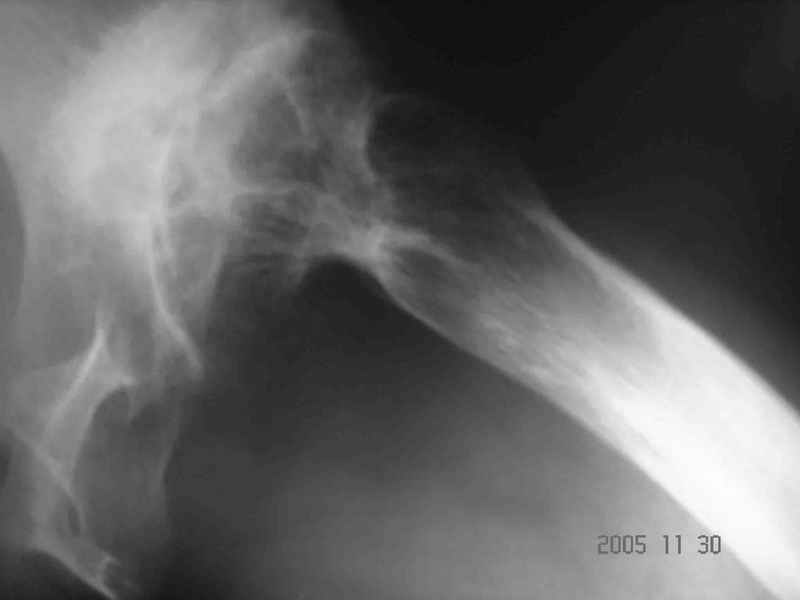

Аксиальный Р-снимок

Re: Диспластический коксартроз

Вы вполне можете обойтись стандартной клиновидной ножкой, определенные сложности будут в установке вертлужного компонента. Если есть вопросы, не стесняйтесь, спрашивайте.